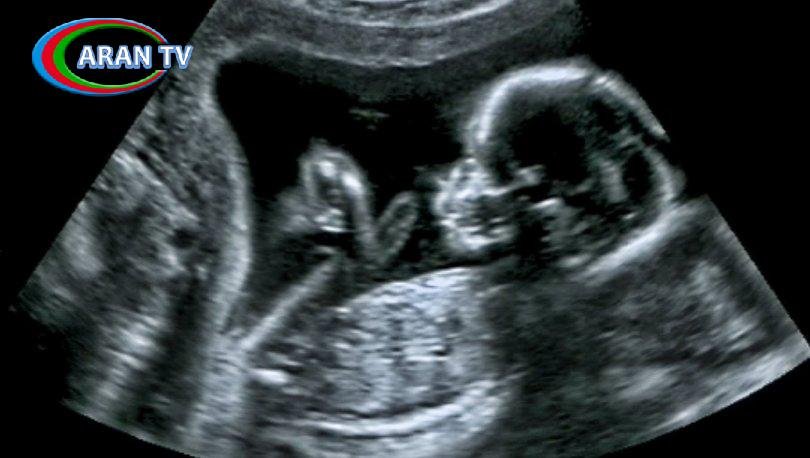

ARANTV.AZ xəbər verir ki, onun sözlərinə görə, təxminən 2045-ci ildə sperma sayı sıfıra çatacaq: “Gələcəkdə insanlar doğmaq, ana olmaq krizisi ilə qarşı-qarşıya qalacaq. Araşdırmalara görə, qərbdəki sperma sayı 1973-2011-ci illər arasında 59 faiz azalıb. Bu vəziyyət insanın sağ qalmasına təhlükə yaratmadan daha uzun müddət davam edə bilməz. Hazırda insanlar daha çox kimyəvi məhsullara məruz qalır. Bu isə insanlarda bir sıra problemlərə səbəb olur”.